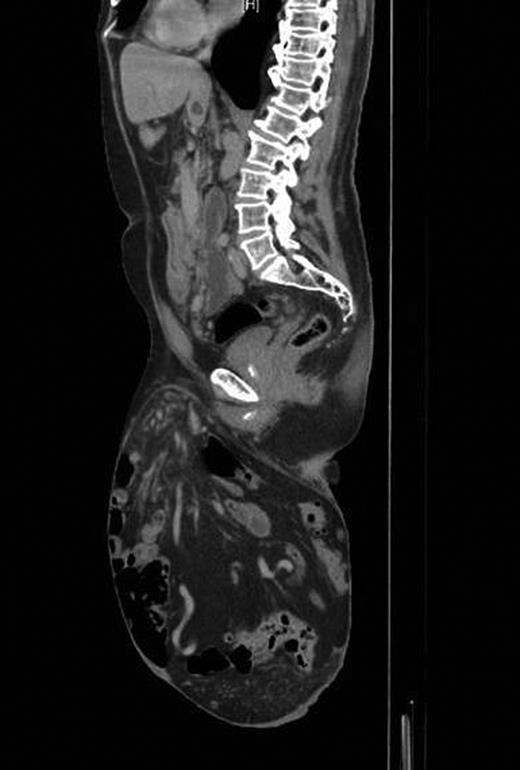

A contrast-enhanced computed tomography (CT) scan revealed the hernia sac containing most of the colon and small bowel with only the rectum, proximal jejunum and duodenum lying within the abdomen (Fig. 2). Preoperative anaesthetic assessment was completed and the patient was admitted to hospital 2 days preoperatively for bowel preparation. After a midline laparotomy, attempts at reduction were not successful even after dividing the inguinal ligament. Reduction in hernia contents was possible only after completely dividing the lower end of the left rectus abdominis muscle. The hernial sac was then dissected and resected. Then, component separation technique was performed laparoscopically using the same balloons used for total extra peritoneal (TEP repair for inguinal hernias). A 2 cm transverse incision located just under the rib cage in the mid-clavicular line was deepened until the area just posterior to the external oblique was entered. The large balloon was inserted in this space in the direction of the pelvis and inflated under laparoscopic guidance to create the space between the external and internal obliques. This was followed by the triangular balloon and insufflation was started at pressure of 11 mmHg under laparoscopic control. A lateral incision to introduce a 5 mm trocar is performed and a pair of laparoscopic scissors introduced to make a longitudinal incision in the external oblique aponeurosis extending along the mid-clavicular line from the rib cage to the inguinal ligament. The same is repeated on the other side. The hernia defect was then repaired extraperitoneally using a large polypropylene mesh extending from the anterior superior iliac spine to the symphysis pubis. Both the inguinal ligament and rectus abdominis muscle were repaired. The procedure ended by mass closure of the laparotomy incision.

On follow-up after 8 weeks, the patient was in a very good general condition with intact hernia repair and laparotomy wound. He was found to have a moderate scrotal swelling (Fig. 3) which proved by CT scan to be a postoperative seroma (Fig. 4) which was managed conservatively.

Postoperative CT scan showing intact repair and clear fluid in the scrotum.